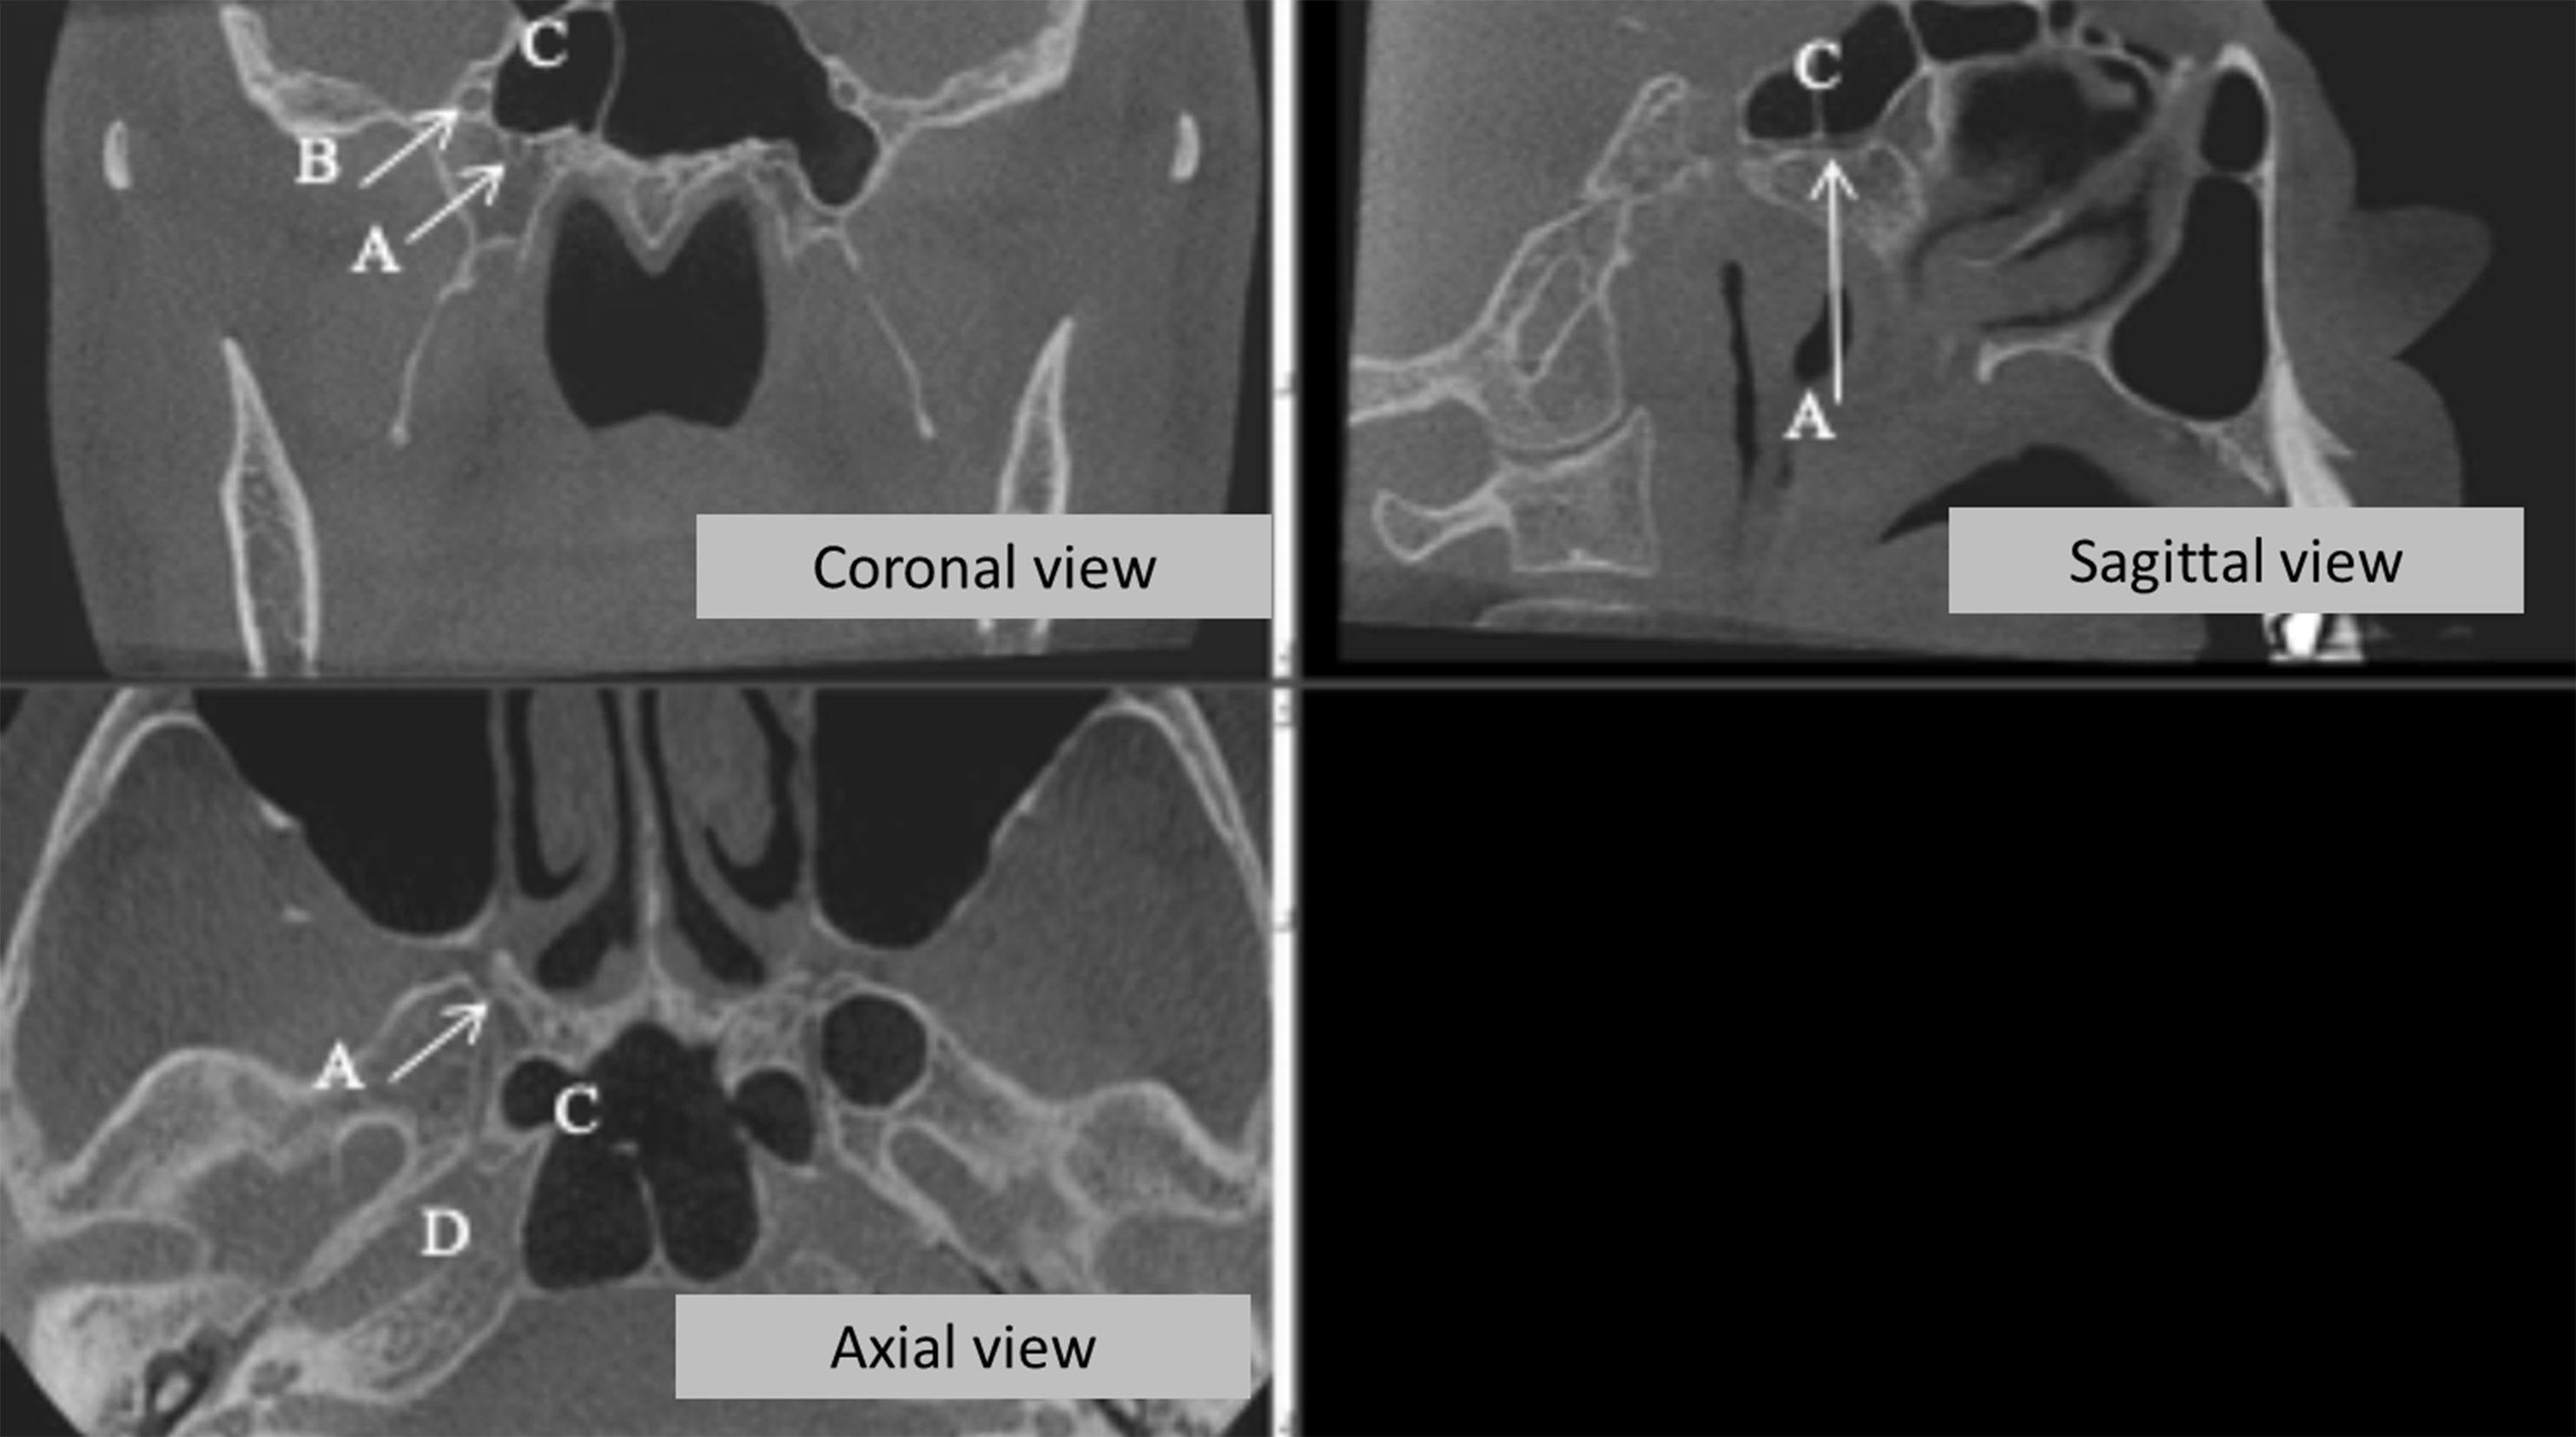

Objective: The aim of this study was to evaluate the pterygoid canal (PC) by Cone Beam Computed Tomography (CBCT), establishing its configuration and proximity with anatomical structures. Material and Methods: We evaluated 398 CBCT exams, all from a public University radiology clinic archive. Four parameters were evaluated: single or double PC, distance between PC and the inferior part of the sphenoid sinus (SS), ratio of PC and SS and the distance between the PC and the foramen rotundum. Results: It was observed that most of the PC of the sample presented simple morphology, the most frequent type of relationship between the PC and the SS on both sides was the close contact with the wall. Among the cases that there were some distances between the PC and the inferior wall of the SS, the mean of this distance did not exceed 3.20 mm, being the left side (3.03 mm) slightly closer than the right (3.20 mm). Finally, the distances between the PC and the corresponding Foramen Rotundum are presented with mean values of 5.87 mm for the right side and 6.31 mm for the left side. Conclusion: CBCT examination is of paramount importance for PC identification; once in the studied sample, the mean values found evidence the close relation between the PC and the SS.